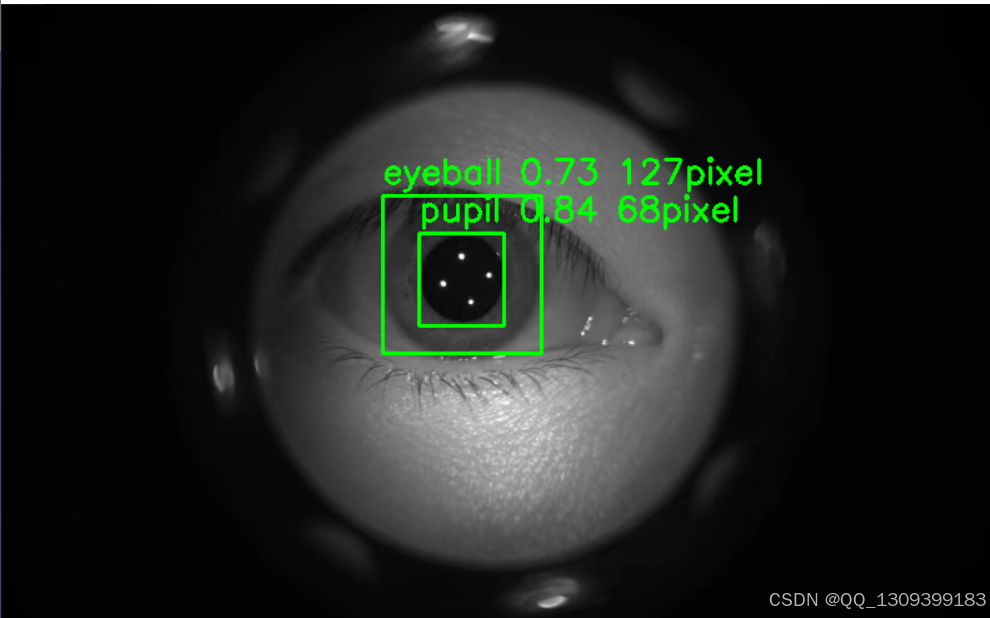

4. 直径计算

几何测量

一旦模型能够准确地定位瞳孔和眼球,就可以基于预测结果计算其直径。对于圆形物体来说,可以直接测量两个最远点之间的距离;对于非标准形状,则可能需要用椭圆拟合或者其他数学方法来估算。

校准

考虑到摄像头的不同焦距和拍摄距离可能导致尺寸失真,因此建议进行适当的校准工作,以保证测量值的准确性。